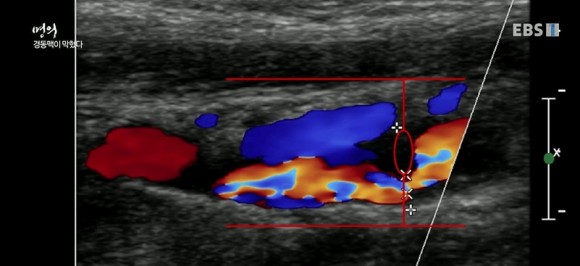

경동맥이 막히는 환자의 초음파 사진과 MRI

가장 간단하고 정확하게 혈관의 이상을 알 수 있는 초음파 검사와 MRI 검사를 실시해 보았습니다. 심장에서 뇌로 가는 혈관은 4개인데 그 중 양쪽 경동맥에서 뇌혈액 공급량의 80%를 담당합니다. 검사상 경동맥의 일부가 좁아져 있는 것이 보입니다.

경동맥은 내막, 중막, 외막의 3중으로 되어 있지만 중요한 것은 혈관벽 두께입니다. 건강한 사람은 내막과 중막 두께를 합치면 0.5~0.9mm인데 만약 1mm가 넘으면 찌꺼기가 쌓여 동맥경화 상태로 봐야 합니다. (심근경색의 2배, 뇌졸중의 5배 증가)